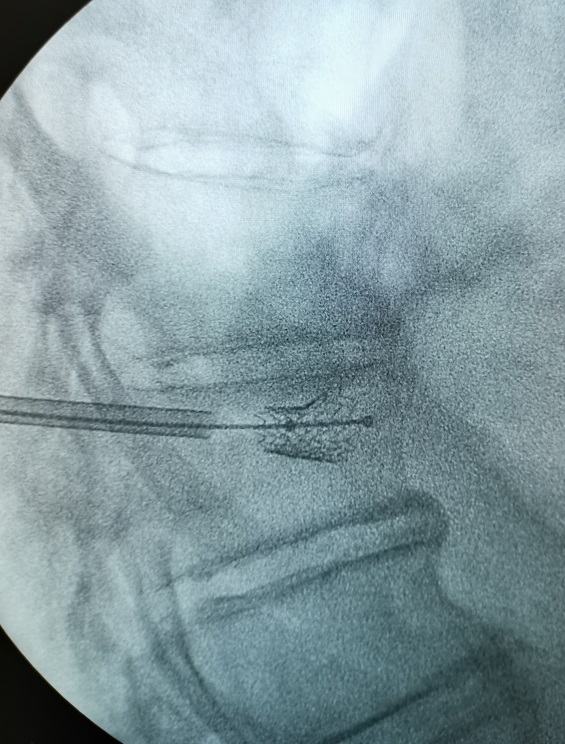

PKP球囊擴(kuò)張應(yīng)用技巧

球囊擴(kuò)張球囊置入傷椎,導(dǎo)管上金色標(biāo)記全部進(jìn)入外鞘。球囊預(yù)擴(kuò)張后取出導(dǎo)絲。術(shù)中球囊體積球囊擴(kuò)張的體積是手術(shù)的關(guān)鍵術(shù)中C臂監(jiān)測球囊擴(kuò)張情況術(shù)者控制體積,監(jiān)視壓力球囊擴(kuò)張,推開周圍組織以產(chǎn)生空間術(shù)中球囊壓力指征球囊壓力直接來源于周圍松質(zhì)骨和軟組織:預(yù)擴(kuò)張:50~70psi,可拔出內(nèi)芯。擴(kuò)張松質(zhì)骨:70~300psi。球囊最終壓力不超過300psi。球囊擴(kuò)張,擠壓周圍松質(zhì)骨產(chǎn)生空間時(shí)壓力明顯增加。骨折復(fù)位后,壓力逐漸下降,延長球囊擴(kuò)張時(shí)間。終止擴(kuò)張球囊的指征椎體高度恢復(fù)至正常;雖無高度恢復(fù)但球囊已擴(kuò)張至終板;球囊已達(dá)到一側(cè)皮質(zhì);擴(kuò)張時(shí)球囊壓力不再降低;已達(dá)到球囊的最大容量4ml或最大壓強(qiáng)20ATM。達(dá)到或出現(xiàn)上述任一項(xiàng)時(shí),即可停止擴(kuò)張骨水泥注入骨水泥注入技巧骨水泥粉劑和液劑充分混合好后用注射器將骨水泥置入骨導(dǎo)向器(骨導(dǎo)向器注入椎體容量1.3ml),等待骨水泥進(jìn)入可注入狀態(tài)。待骨水泥出現(xiàn)“拉絲”現(xiàn)象,可將骨水泥注入椎體剛注入0.2-0.3ml時(shí)透視確認(rèn)骨水泥彌散方向是否安全。安全則可繼續(xù)緩慢推入骨水泥。每注入0.5ml需透視觀察,同時(shí)關(guān)注病人血壓等情況。掌握骨水泥的量,確保安全。(注入量略多于最終膨脹容積)